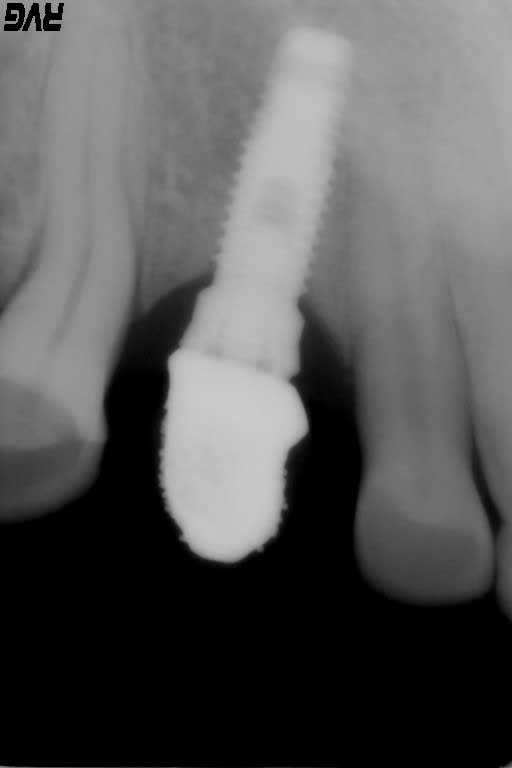

Bjr, avez vous une idée de la marque et référence de cet implant mystère posé il y a une vingtaine d'année ?

Merci pour votre aide et de votre indulgence pour la qualité de la rétro.

et si toi tu ne trouves pas .... ! pourtant le col de l'implant est bien particulier, j'ai fait le tour de la bibliothèque mais ça ne matche pas.

en effet le col est bien particulier, et j'ai rien trouvé qui matche...d'autant qu'il me semble voir un trou à l'apex, et là c'est encore pire j'ai moins de choix et toujours rien qui correspond

le seul truc qui pourrait "coller" mais c'est tiré par les cheveux et la qualité de la radio n'est pas assez bonne pour vérifier çà....c'est que ce serait un Nobel mk1 sur lequel serait mis un multiunit ou un pilier dessus qu'on ne verrait pas du fait de l'axe et le flou de la radio

merci d'avoir pris le temps Pluton, j'ai un cbct et il y a bien un trou à l'apex.

je pense aussi que tu as raison, le col de l'implant doit s'arrêter à la partie droite et ensuite l'évasement doit être un pilier.

Le patient a finalement retrouvé une référence et ce serai un Steri-os vis 4.5x12mm avec un pilier uni par dessus pour expliquer l'image du col ainsi rallongé.

A priori la marque n'existe plus donc j'ai pas fini de galérer.

c'est bien çà....après sterioss ou Nobel sans une rétro tiptop pour bien voir le connexion c'était difficile de différencier...